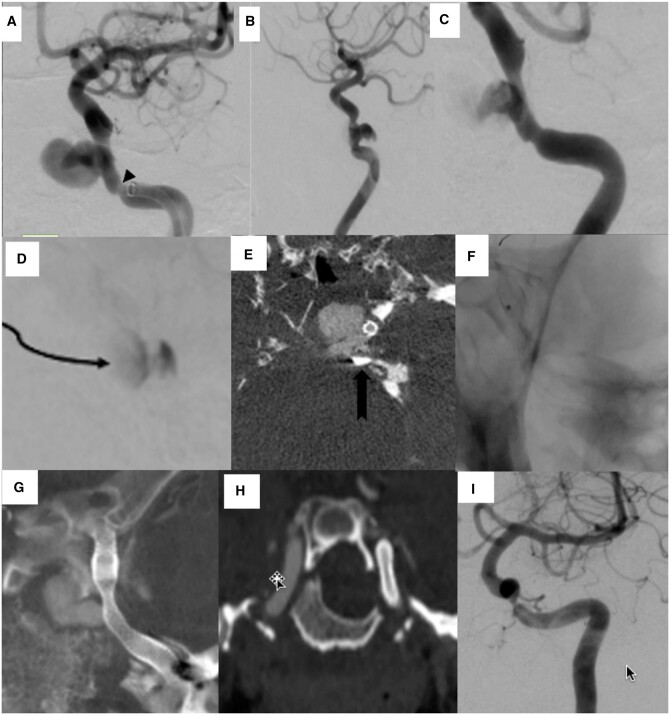

The coronavirus pandemic is now a public health emergency and has spread to nearly 206 countries across the globe. This novel disease has shaken the psycho-social, economic, and medical infrastructure of India. This has become even more challenging, considering the country's huge population. With the increase in the number of coronavirus disease (COVID) cases, our country has seen an unforeseen, unprecedented rise in a potential life and organ-threatening disease-mucormycosis. Mucormycosis is a deadly, extremely morbid, possibly life-threatening, and most feared complication of the coronavirus, caused by environmental molds belonging to the order Mucorales. Here, we report 2 cases of massive epistaxis due to internal carotid artery (ICA) pseudoaneurysm secondary to mucormycosis, post-COVID-19 pneumonia, which was managed by the endovascular route. To the best of our knowledge, there is very sparse literature available describing endovascular treatment of intracranial ICA pseudoaneurysm in a patient with COVID-induced mucormycosis.